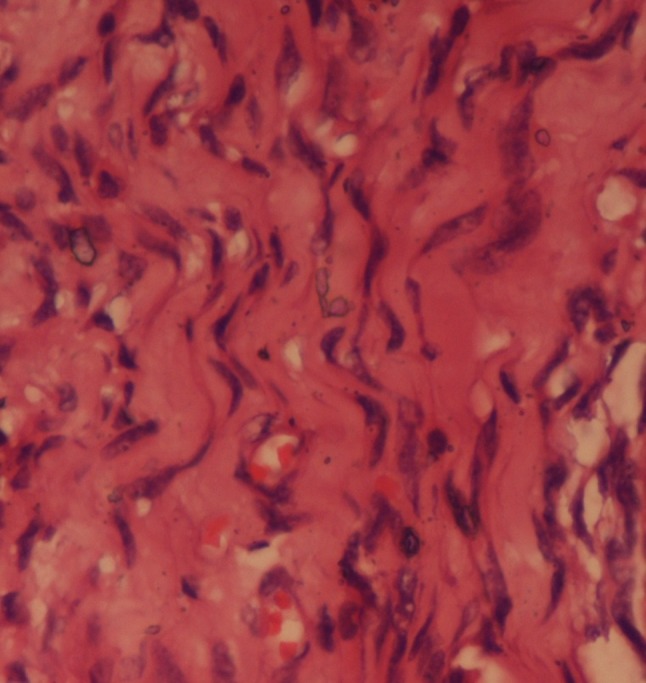

Herein, we report the case of a 16-year-old female who presented to the orthopaedics clinic with the complaint of a painless soft tissue swelling involving the right ankle and foot. She first noted the swelling at about 8 years of age. Initially, it was small, but later, the lesion gradually painlessly progressed to the present size. It completely surrounded the ankle and the heel region. The involved region experienced overgrowth compared to that on the opposite side. The skin over the swelling was normal with no evidence of any discolouration. On palpation, the temperature of the lesion was not raised. The lesion was soft to touch, but it was not possible to distinguish the margins from the adjacent normal area, suggesting an ill-defined lesion. In consistency with the examination findings, the provisional diagnosis of a vascular malformation was considered. The patient was subjected to ultrasonography. It showed an increase in the thickness of the soft tissue, which appeared hyperechoic, comparable to the adjacent normal fat density with multiple interspersed hypoechoic areas within it (Fig. 1). On colour Doppler evaluation, these hypoechoic areas showed slow flow, which it was better to appreciate on power Doppler (Fig. 2). These findings were consistent with the diagnosis of a vascular malformation. However, the duration of the progression of the supposed vascular malformation and the absence of phleboliths on the ultrasound and the subsequent X-ray raised suspicion regarding the diagnosis of a vascular malformation. A second differential of a neurofibroma was considered. Subsequently, a biopsy was conducted. It showed elongated spindle cells with poorly defined, pale eosinophilic cytoplasm and tapering, wavy, or buckled nuclei admixed with a few small nerve fibres (Fig. 3). Immunohistochemistry showed positivity for S-100 (Fig. 4). These findings were consistent with the diagnosis of diffuse neurofibroma.

Fig. 3.

Microscopic tissue section shows elongated spindle cells with poorly defined, pale eosinophilic cytoplasm and tapering, wavy, or buckled nuclei admixed with a few small nerve fibres. Haematoxylin and Eosin × 40 ×